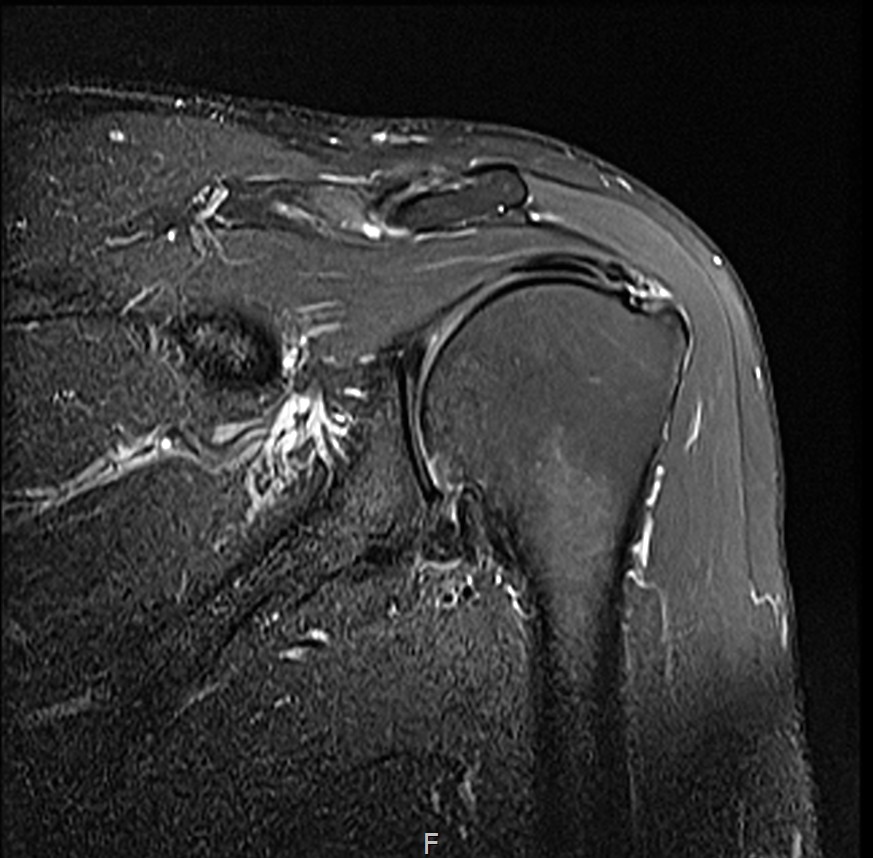

MRI를 검토해보았습니다.

회전근개 극상건의 점액낭면측(bursal-side) 부분파열. 처음보다 파열 범위가 약간 넓어져 있었고, 인대가 얇아진 소견도 보였습니다.

MRI: 극상건 점액낭면측 부분파열

인대 두께: 4.2mm (정상 5~6mm보다 얇음)

1년간 주사치료 3회, 반복 재발